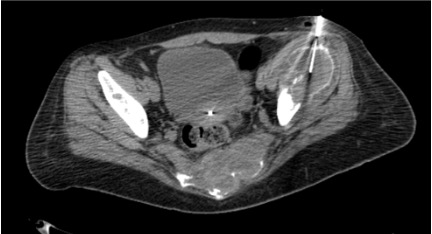

View CT bone biopsy

CT showing bone biopsy needle advanced through cortex into lesion